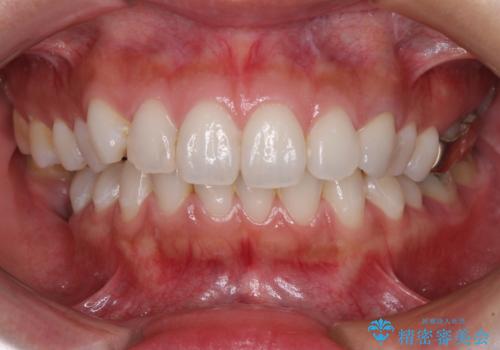

前歯1本の治療では、オールセラミッククラウンといえども周囲と調和しなければ自然な仕上がりにはなりません。

今回は既製の色調のセラミックを選択されましたが、もっと色合いにこだわりたい場合には、オーダーメイドタイプのセラミッククラウンをご選択いただいています。